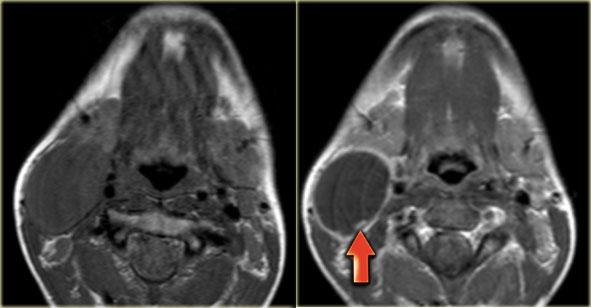

Paraganglioma: Hình ảnh MRI chuỗi xung T1W có tiêm thuốc tương phản từ Gadolinium tại mức thanh quản trên thanh môn

Paraganglioma

Bước 1: Xác định khoang

Bên trái là hình ảnh một bệnh nhân có khối sưng ở bên trái cổ.

Hãy quan sát hình ảnh MRI tại mức thanh quản trên thanh môn và xác định tổn thương nằm trong khoang nào.

Sau đó tiếp tục đọc.

Khối sưng nằm tập trung giữa động mạch cảnh ngoài và động mạch cảnh trong.

Lưu ý rằng các mạch máu này bị chèn ép.

Rõ ràng tổn thương này phải nằm trong khoang cảnh.

Cần lưu ý rằng có một tổn thương nhỏ hơn nhưng có hình thái tương tự, nằm ở khoang cảnh bên phải.